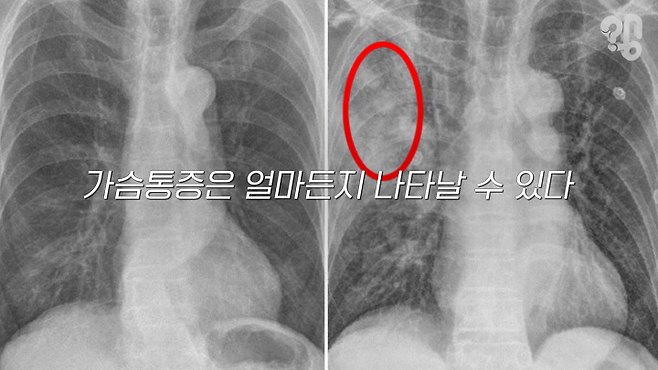

기흉의 가장 흔한 증상이 가슴통증이 가장 흔한 증상으로 보통 숨을 쉴 때마다 가슴 안쪽이 뻐근해진다.

갑자기 나타나는 경우가 많지만 서서히 발생하기도 하고, 운동과 상관없이 생기기도 한다